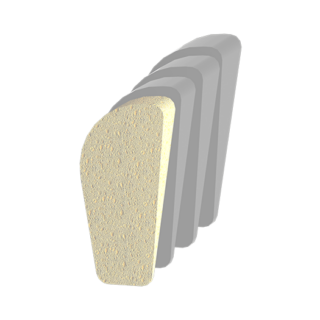

A Unique Implant Solution made possible through the use of Additive Manufacturing

Built with LatTi-Structure®

3D printed Ti6Al4V Titanium ELI

Available in 4.5, 5.5, and 6.5mm size options

Built with LatTi-Structure®

3D printed Ti6Al4V Titanium ELI

Available in 4.5, 5.5, and 6.5mm size options

The ADDITIVE ORTHOPAEDICS® Bone Wedge System offers a porous titanium wedge that provides an alternative to allograft/autograft bone for a Cotton Osteotomy for plantarflexion of the first ray. The system includes procedure specific shaped Ti6AI4V Titanium ELI wedges in nine sizes. The wedges are additively manufactured and feature a propriety 79% porous lattice structure.